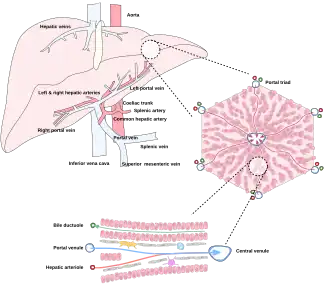

The liver is connected to two large blood vessels: the hepatic artery and the portal vein. The hepatic artery carries oxygen-rich blood from the aorta via the celiac trunk, whereas the portal vein carries blood rich in digested nutrients from the entire gastrointestinal tract and also from the spleen and pancreas.[11] These blood vessels subdivide into small capillaries known as liver sinusoids, which then lead to hepatic lobules.

Hepatic lobules are the functional units of the liver. Each lobule is made up of millions of hepatocytes, which are the basic metabolic cells. The lobules are held together by a fine, dense, irregular, fibroelastic connective tissue layer extending from the fibrous capsule covering the entire liver known as Glisson's capsule after British doctor Francis Glisson.[4] This tissue extends into the structure of the liver by accompanying the blood vessels, ducts, and nerves at the hepatic hilum. The whole surface of the liver, except for the bare area, is covered in a serous coat derived from the peritoneum, and this firmly adheres to the inner Glisson's capsule.

Microscopic anatomy

Microscopically, each liver lobe is seen to be made up of hepatic lobules. The lobules are roughly hexagonal, and consist of plates of hepatocytes, and sinusoids radiating from a central vein towards an imaginary perimeter of interlobular portal triads.[24] The central vein joins to the hepatic vein to carry blood out from the liver. A distinctive component of a lobule is the portal triad, which can be found running along each of the lobule's corners. The portal triad consists of the hepatic artery, the portal vein, and the common bile duct.[25] The triad may be seen on a liver ultrasound, as a Mickey Mouse sign with the portal vein as the head, and the hepatic artery, and the common bile duct as the ears.[26]

Histology, the study of microscopic anatomy, shows two major types of liver cell: parenchymal cells and nonparenchymal cells. About 70–85% of the liver volume is occupied by parenchymal hepatocytes. Nonparenchymal cells constitute 40% of the total number of liver cells but only 6.5% of its volume.[27] The liver sinusoids are lined with two types of cell, sinusoidal endothelial cells, and phagocytic Kupffer cells.[28] Hepatic stellate cells are nonparenchymal cells found in the perisinusoidal space, between a sinusoid and a hepatocyte.[27] Additionally, intrahepatic lymphocytes are often present in the sinusoidal lumen.[27]

Blood supply

The liver gets its blood supply from the hepatic portal vein and hepatic arteries. The hepatic portal vein delivers around 75% of the liver's blood supply and carries venous blood drained from the spleen, gastrointestinal tract, and its associated organs. The hepatic arteries supply arterial blood to the liver, accounting for the remaining quarter of its blood flow. Oxygen is provided from both sources; about half of the liver's oxygen demand is met by the hepatic portal vein, and half is met by the hepatic arteries.[46] The hepatic artery also has both alpha- and beta-adrenergic receptors; therefore, flow through the artery is controlled, in part, by the splanchnic nerves of the autonomic nervous system.

Blood flows through the liver sinusoids and empties into the central vein of each lobule. The central veins coalesce into hepatic veins, which leave the liver and drain into the inferior vena cava.[47]

The liver and its veins -

Diagram of liver, lobule, and portal tract and their inter-relations